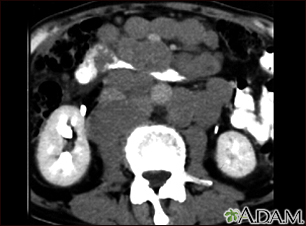

Lymphoma, malignant - CT scan